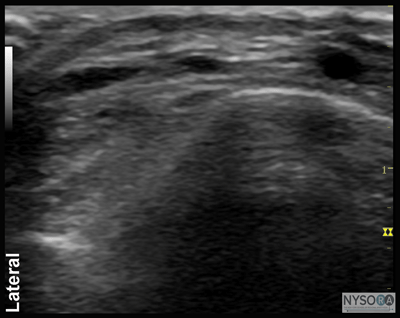

Figure 1: Block of the posterior tibial nerve using an out-of-plane technique. Essentials

![]() Figure 2: Cross-sectional anatomy of the posterior tibial nerve at the level of the ankle. Shown are posterior tibial artery (PTA) and vein (PTV) behind the medial malleolus (Med. Mall.) The posterior tibial nerve (PTN) is just posterior and superficial to the posterior tibial vessels. General Considerations Using an ultrasound-guided technique affords a practitioner the ability to reduce the volume of local anesthetic required for ankle blockade. Because the nerves involved are located relatively close to the surface, ankle blocks are easy to perform technically; however, knowledge of the anatomy of the ankle is essential to ensure success. Ultrasound Anatomy Ankle block involves anesthetizing five separate nerves: 2 deep nerves and 3 superficial nerves. The 2 deep nerves are tibial (TN) and deep peroneal nerve (DPN). The superficial nerves are superficial peroneal, sural and saphenous. All nerves except saphenous nerve are terminal branches of the sciatic nerve; saphenous nerve is a cutaneous extension of the femoral nerve. Tibial Nerve The tibial nerve is the largest of the five nerves at the ankle level and provides innervation to the heel and sole of the foot. With a linear transducer placed transversely at (or just proximal to) the level of the medial malleolus, the nerve can be seen immediately posterior to the posterior tibial artery (Figures 1, 2, and 3A and B). Color Doppler can be very useful in depicting the posterior tibial artery when it is not readily apparent. The nerve typically appears hyperechoic with dark stippling. A useful mnemonic for the relevant structures in the vicinity is Tom, Dick ANd Harry, which refers to, from anterior to posterior, the tibialis anterior tendon, flexor digitorum longus tendon, artery/nerve/ vein, and flexor hallucis longus tendon. These tendons can resemble the nerve in appearance, which can be confusing. The nerve's intimate relationship with the artery should be kept in mind to avoid misidentification.